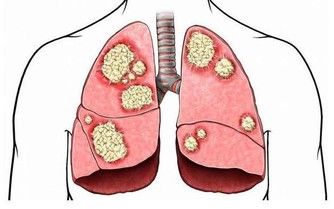

長生不老的秘訣:「要叫人不死、 腸中須無屎」。 醫家自古就提倡「早吃好、中吃飽、晚吃少、晚餐不吃最為好」,並特彆強調「人要長生、腸要常清」。 【現代醫學告訴我們】 人的腸道有8-10米長,並且千褶百皺,平均每隔3.5公分就有一個彎折,人們即使每天都排泄,也總會有一些食物殘渣滯留在腸道的褶皺內,它們在細菌的作用下乾結、腐敗、發酵。

日積月累,這些食物殘渣最終形成厚達5-7毫米,重達5-6公斤的黑色、惡臭、有毒的物質,並像「銹」一樣牢牢地粘連在腸壁上,其堅硬程度與輪胎相似,它們慢慢侵蝕著我們的身體,人們習慣稱之為宿便。

這些宿便堆積在腸道內發酵、腐敗,並不斷產生各種毒素、毒氣,被腸粘膜吸收到血液並輸送到身體各個細胞,首先造成腸內環境惡化、腸胃功能紊亂,既而引發內分泌失調、新陳代謝紊亂,最後引發各種病症,促使人體衰老與死亡。 可以毫不誇張地說,腸道問題是人體萬病之源。 我國古代中醫里有個「陰陽水清腸方」,就是專門用來清除宿便,防止結腸功能失調,可以讓人「不死」的秘法。李時珍《本草綱目·水·生熟湯》:「以新汲水百沸湯合一盞和勻,故曰生熟。今人謂之陰陽水」。 此句是指:從井裡新提的生水和剛煮開的水各一碗混和均勻便是「陰陽水」。 然現代社會水污染嚴重,誰敢冒著「污染水」中毒的風險去喝生水? 【其具體方法】 一、陰陽水清腸方: